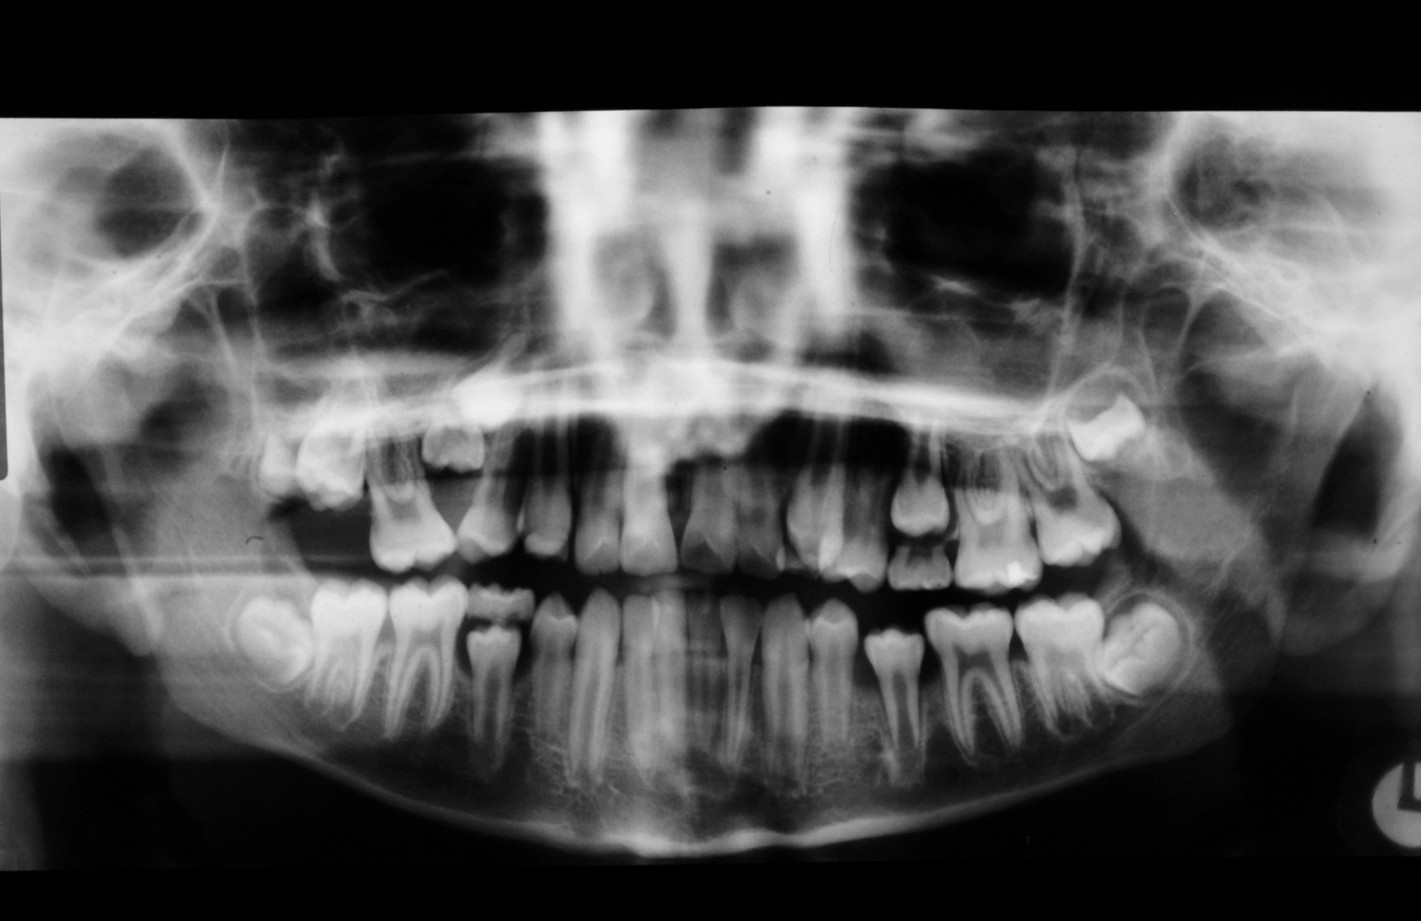

Figure 2 and Figure 3 illustrate examples of indications for removal of a third molar tooth.

Assessment of the tooth is both clinical and radiographic. If somebody presents in pain, it is important to establish that this is coming from the third molar and not elsewhere. Pain is often vague, poorly localised and may be referred from another tooth, or as part of facial arthromyalgia (condition affecting the jaw joint). A dental panoramic radiograph is ideal as it helps to assess all the teeth at once. The health of the adjacent molars may influence the decision whether to remove the third molar or not. Large crowns or old restorations are all at risk of dislodgement during surgery. It is also worth considering whether alternative treatment options are available. For instance, pericoronitis due to an over-erupted upper third molar may be dealt with by extracting that tooth only, with or without operculectomy. In the presence of other teeth of poor prognosis, will it be better in the long term to save the third molar which may be used as a denture or bridge abutment in the future?

These points help to determine whether the tooth can be simply elevated or will need a surgical approach. A series of radiographs depicted in Figure 4 to Figure 8 illustrate these points further.